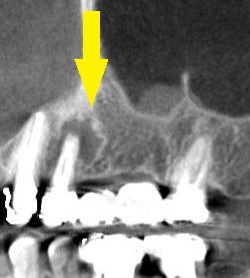

CTを撮ってみると、破折した歯の周囲は骨がかなり吸収されており、状態は良くありませんでした(下の写真上段右)。

この状態でも、なんとか抜歯してそのままインプラントを埋入する、抜歯即時埋入が可能と考え、

下の写真中段が手術前のCT、下段が手術後のCTです。